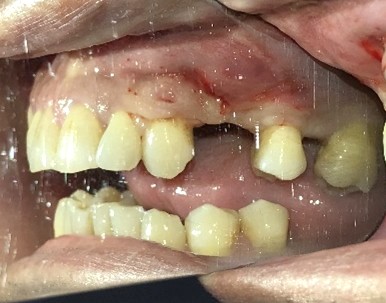

Before

歯根が真っ二つに割れていました

抜いた歯

【抜歯後】

After